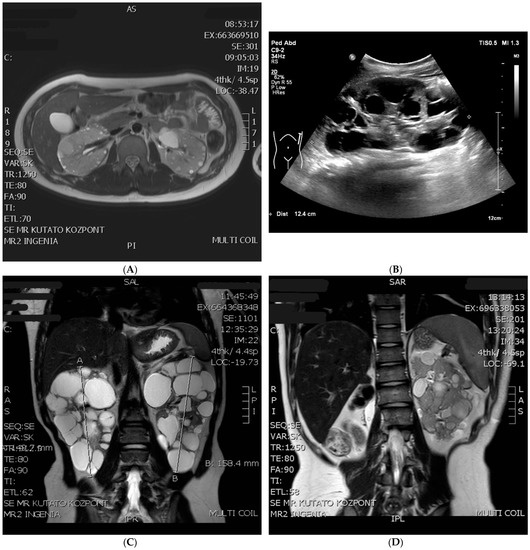

The Importance of Genetic Testing in the Differential Diagnosis of Atypical TSC2-PKD1 Contiguous Gene Syndrome—Case Series

Background: In clinical practice, the possible diagnosis of tuberous sclerosis or polycystic kidney disease is primarily based on clinical criteria, which can later be verified by genetic testing. But in the case of TSC2/PKD1 contiguous gene syndrome...